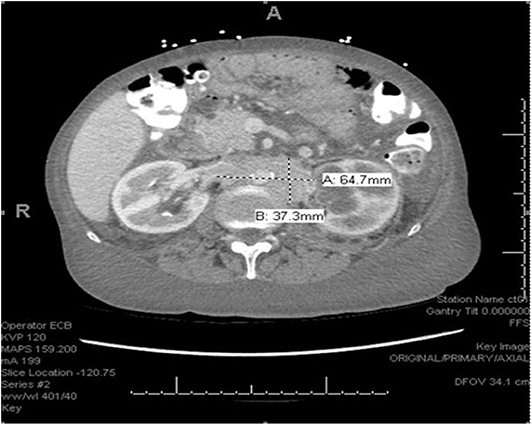

We describe the case of a 65-years-old female with no significant past medical history who was admitted to the hospital with complaints of lower extremity swelling and dyspnea on exertion. She also admitted to a 50 pound unintentional weight loss over the 3 years prior to admission. A CT of the chest, abdomen and pelvis with contrast (Figure 1) revealed extensive retroperitoneal adenopathy with the largest conglomerate of lymph nodes at the level of the renal hila measuring 6.5 × 3.7 cm with resultant severe left hydroureteronephrosis. Diffuse anasarca was also noted with small bilateral pleural effusions and a small pericardial effusion. Evaluation of the gastrointestinal tract revealed distorted mural thickening of the distal and terminal ileum as well as the proximal ascending colon.

FIGURE 1

Figure 1. CT scan with extensive retroperitoneal adenopathy.